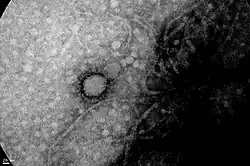

Image of SARS-CoV-2 taken by the Cell Biology and Neuroscience Institute "Professor E. de Robertis", UBA-CONICET.